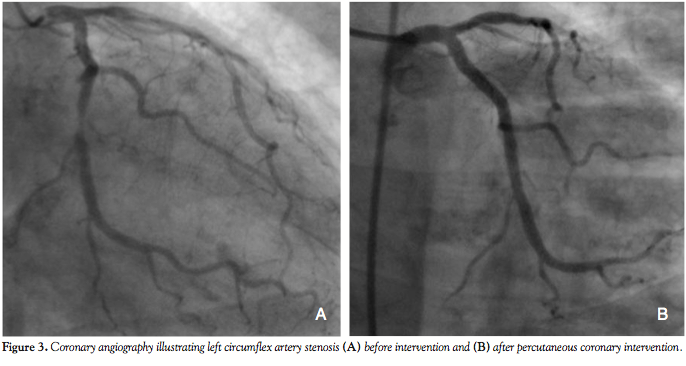

With a calculated logistic Euroscore of 25% (based on the patient’s age and sex, her presentation with an acute myocardial infarction and her critical pre-operative state), the decision was made for an invasive assessment of the coronary status with the possibility of performing PCI and TAVI in a combined percutaneous approach. The procedure was performed under conscious sedation and angiographic guidance. Coronary angiography revealed two-vessel disease, with

an 80% left circumflex artery (LCX) stenosis and an ostial 80% right coronary artery (RCA) stenosis (Figures 3A and 4A). Aortic root angiography revealed trivial aortic regurgitation and an aortic annular diameter of 24 mm, and peripheral angiography showed adequately-sized common femoral and iliac arteries with no significant stenosis or kinking. Successful percutaneous coronary intervention with implantation of two zotarolimus-eluting stents was achieved in

both the LCX and RCA (Figures 3B and 4B). Thereafter, an 18 Fr sheath was advanced into the right femoral artery under fluoroscopic guidance. The calcified stenotic aortic valve was crossed by a straight Terumo wire (Terumo, Tokyo, Japan) with the help of an Amplatz left catheter. A pigtail catheter was then advanced into the left ventricle and pressure tracings for left ventricle and aorta were simultaneously measured (Figure 5A). Then, a stiff Meier back-up wire (Boston Scientific, Natick, Massachusetts) was placed into the left ventricle and balloon aortic valvuloplasty was performed with a 22 x 60 mm Tyshak II balloon